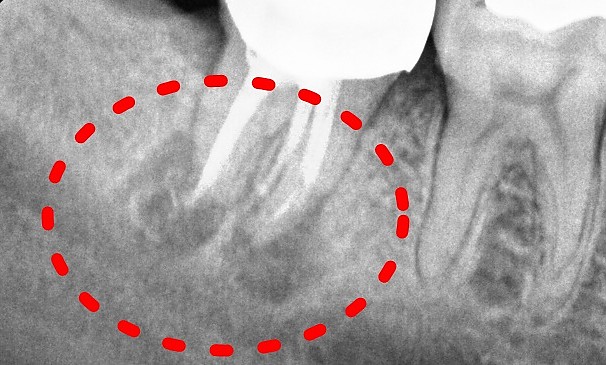

자가치아재식립술이란 치아에 염증이 심하거나 신경치료 된 치아에 어떤 문제가 생겼을 때 해당 치아를 조심스럽고 안정적으로 발치한 후, 구강 밖에서 염증이나 병든 부분을 깨끗하게 제거 하고 뽑았던 치아는 특수 재료로 처리한 다음에 원래 있었던 자리로 다시 조심스럽게 식립하여 치아를 살리는 치료법입니다.

치료 전